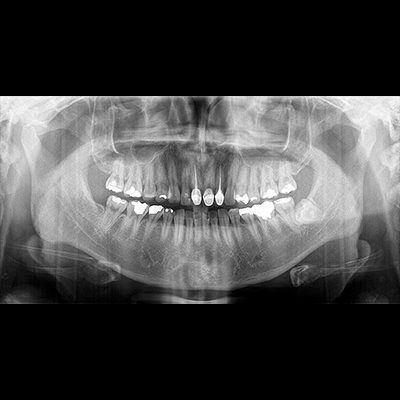

PAPAYA 3D

Diaqnostik kompyuterli erqonomik rentgen sistemi

-3D CT, Panorama

-Çoxsaylı -FOV seçimi (4×5, 14×14)

-Açıq yerləşdirmə (üzbə - üz)

-Çoxsaylı Fokuslanma

-70um görüntülü ENDO rejim